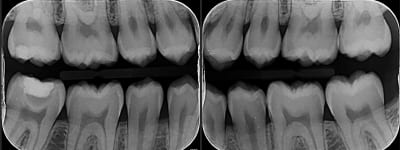

ci joint les radios, pour la 47 il ya une résine avec un fond de cavité

C est quoi ce fond de cavité qui est totalement radio-transparent ???

Clairement... C est a peine moins radio opaque que la dentine. La c est quand même très très radio clair...

Pour moi la c est de la biocarix... ;)

Non ça c est la projection de la convexité de la racine distale qui crée une zone radioclaire.

un peu trop radio clair à mon gout pour etre honnete....